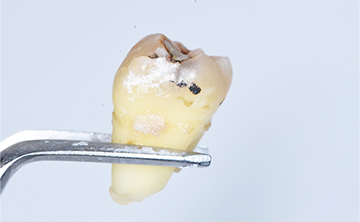

虫歯を放置した場合の抜歯後の歯の写真

最終的にそれでも放置しておくと膿がどんどん溜まっていくので、顔や首などが腫れ上がってしまい発熱が続き最終的には、救急に運ばれて切開排膿することになります。